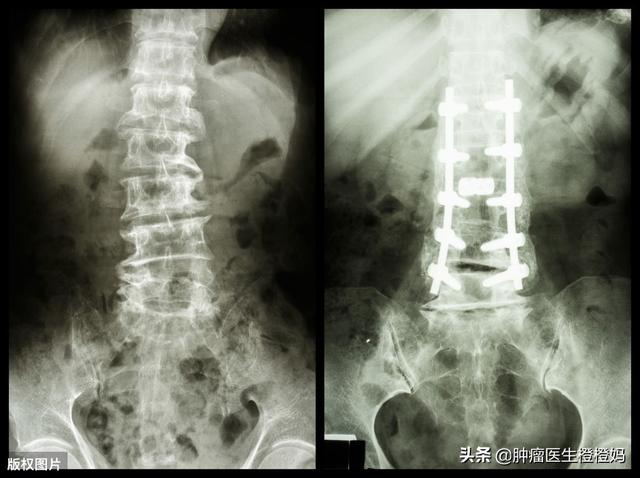

- 骨折があれば、整形外科医の助けを借りなければなりません。状況によっては、大腿骨固定や椎体セメント充填などをしなければならないかもしれません。そして怪我を悪化させないためには、骨折部位の動きを避けることが重要である。

今回は、私の反対を押し切って、ハイと息子が私をがん病院に担ぎ込んだ。CTスキャンの結果、骨転移が腰椎の骨折を引き起こしていた。医師の指示で放射線治療を始めるしかなかった。毎日、息子に車椅子を押してもらい、放射線治療室まで運んでもらった。私の体が耐えられなかったため、合計20回の治療を受けなければならず、終了までに2カ月近くかかった。